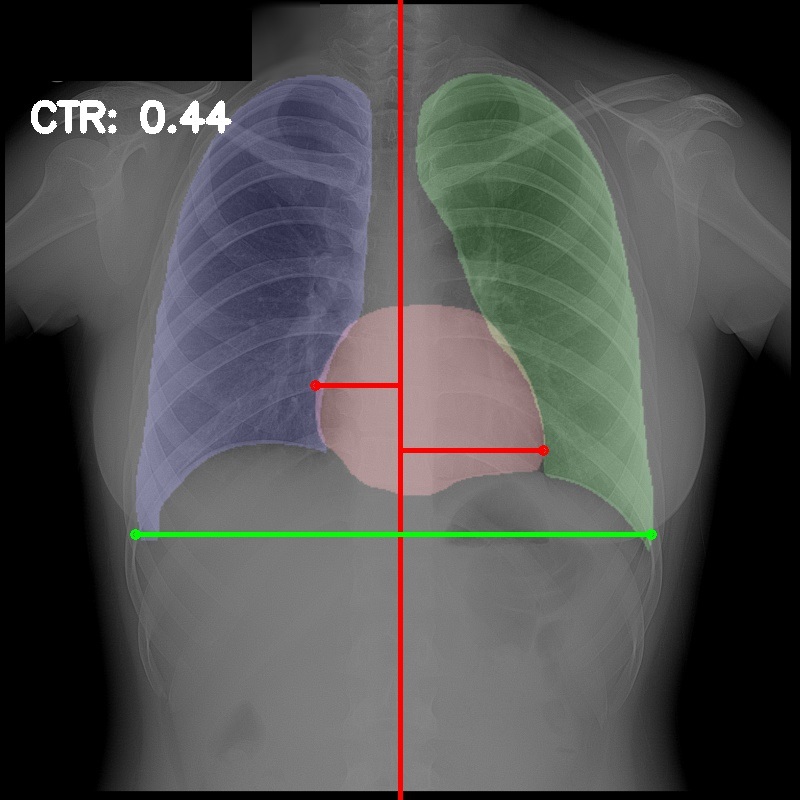

Chest radiography is the most common tool for detecting cardiomegaly due to the low cost and high availability of devices to obtain chest X-ray images. From chest X-ray images, radiologists employ CTR as one of the most important indicators of cardiomegaly due to the simplicity of the calculation. CTR of a chest X-ray image is calculated as cardiac diameter (the diameter of the heart) divided by the thoracic diameter (the diameter of the chest). Specifically, CTR can be calculated from three measurements, , the midline-to-right heart diameter, , the midline-to-left heart diameter, and , the internal diameter of chest [2, 3], as

| (1) |

where and is measured from the greatest perpendicular diameter from midline to right and left heart border, respectively. Figure 1 visualizes the details of CTR calculation. A CTR value of is generally considered to indicate the upper limit of normal.

3.5 Cardiothoracic Ratio Calculation

After obtaining the masks, we calculate CTR with equation 1. We calculate cardiac diameter, , by finding the extreme points on the x-axis of the heart mask and calculate their x-axis distance. Thoracic diameter, , is calculated from extreme points from the lung mask. Figure 4 demonstrates the calculation of each component.

After obtaining heart and lung segments, we calculated , , and and marked them on the image along with CTR value calculated from Equation 1.

Figure 6 shows examples of our CTR calculation, where CTR values along with their , and measurement points are correctly identified. In this image, cardiomegaly is correctly detected by CTR value of .